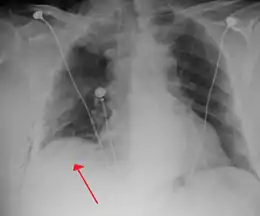

Chest X-ray

A plain chest radiograph, ideally with the X-ray beams being projected from the back (posteroanterior, or "PA"), and during maximal inspiration (holding one's breath), is the most appropriate first investigation.[30] It is not believed that routinely taking images during expiration would confer any benefit.[31] Still, they may be useful in the detection of a pneumothorax when clinical suspicion is high but yet an inspiratory radiograph appears normal.[32] Also, if the PA X-ray does not show a pneumothorax but there is a strong suspicion of one, lateral X-rays (with beams projecting from the side) may be performed, but this is not routine practice.[15][19]

Anteroposterior inspired X-ray, showing subtle left-sided pneumothorax caused by port insertion

Chest X-ray showing a pneumothorax on the right (left in the image), where the absence of lung markings indicates that there is free air inside the chest

Chest X-ray showing the features of pneumothorax on the left side of the person (right in image)

It is not unusual for the mediastinum (the structure between the lungs that contains the heart, great blood vessels, and large airways) to be shifted away from the affected lung due to the pressure differences. This is not equivalent to a tension pneumothorax, which is determined mainly by the constellation of symptoms, hypoxia, and shock.[13]

The size of the pneumothorax (i.e. the volume of air in the pleural space) can be determined with a reasonable degree of accuracy by measuring the distance between the chest wall and the lung. This is relevant to treatment, as smaller pneumothoraces may be managed differently. An air rim of 2 cm means that the pneumothorax occupies about 50% of the hemithorax.[15] British professional guidelines have traditionally stated that the measurement should be performed at the level of the hilum (where blood vessels and airways enter the lung) with 2 cm as the cutoff,[15] while American guidelines state that the measurement should be done at the apex (top) of the lung with 3 cm differentiating between a "small" and a "large" pneumothorax.[33] The latter method may overestimate the size of a pneumothorax if it is located mainly at the apex, which is a common occurrence.[15] The various methods correlate poorly but are the best easily available ways of estimating pneumothorax size.[15][19] CT scanning (see below) can provide a more accurate determination of the size of the pneumothorax, but its routine use in this setting is not recommended.[33]

Not all pneumothoraces are uniform; some only form a pocket of air in a particular place in the chest.[15] Small amounts of fluid may be noted on the chest X-ray (hydropneumothorax); this may be blood (hemopneumothorax).[13] In some cases, the only significant abnormality may be the "deep sulcus sign", in which the normally small space between the chest wall and the diaphragm appears enlarged due to the abnormal presence of fluid.[16]